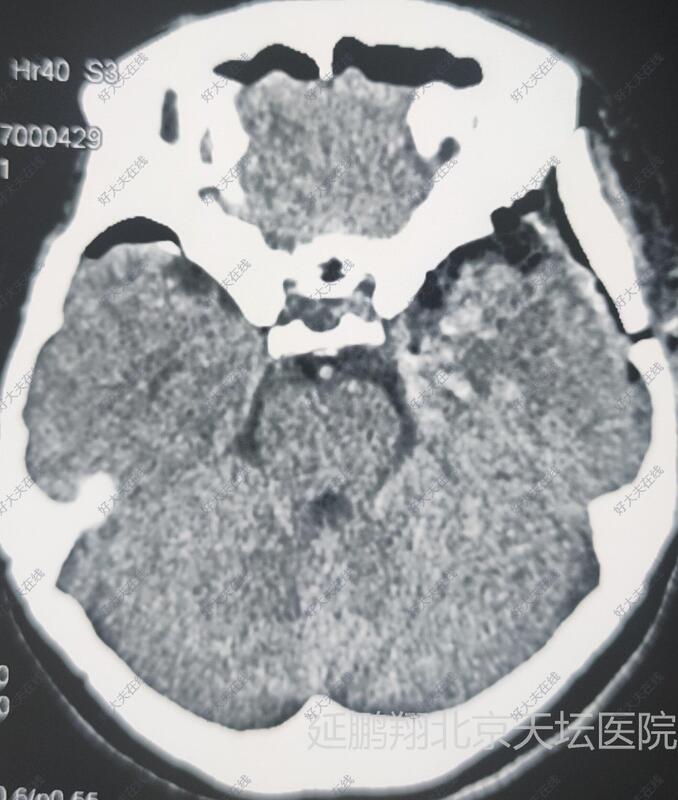

治疗前

女性,48岁。发作性心悸,心烦,头晕11月。CT和MRI显示左侧鞍旁脑膜瘤,与海棉窦及颈内动脉及大脑中动脉关系密切。